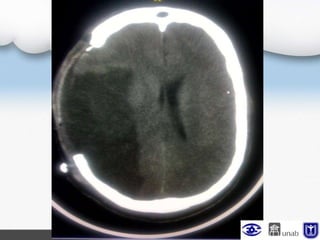

TAC cerebral (UCI)

Neurocirugía

Craniectomía Urgente

Injerto de meninge espinal

Se observa fungus cerebral leve